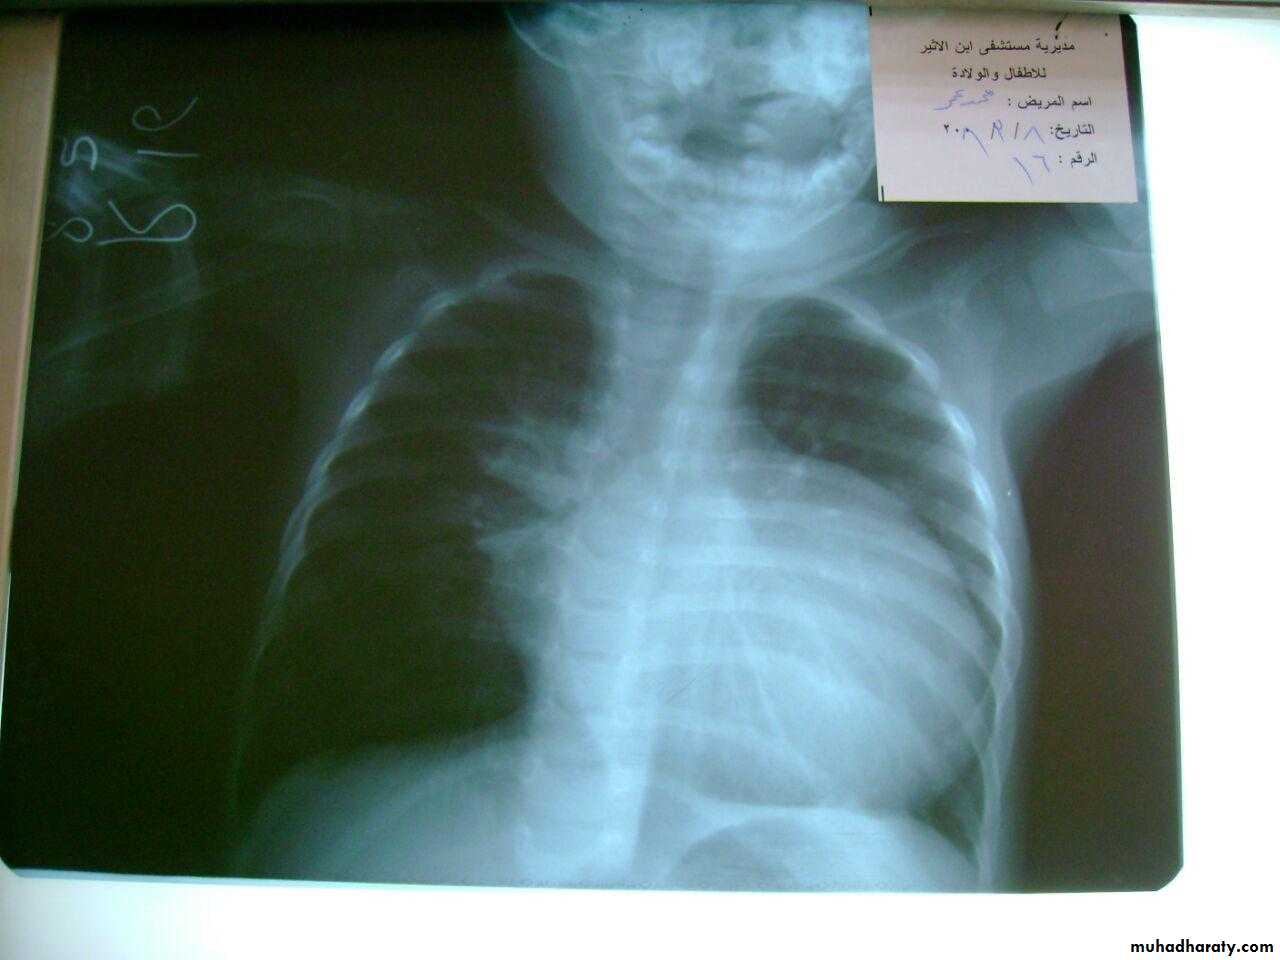

3 month infant presented with cough & dyspnea

Xray shows hyperinflated chest (depresed diaphragm , > 6 ribsMay be bronchiolitis

Hyperinflated chest